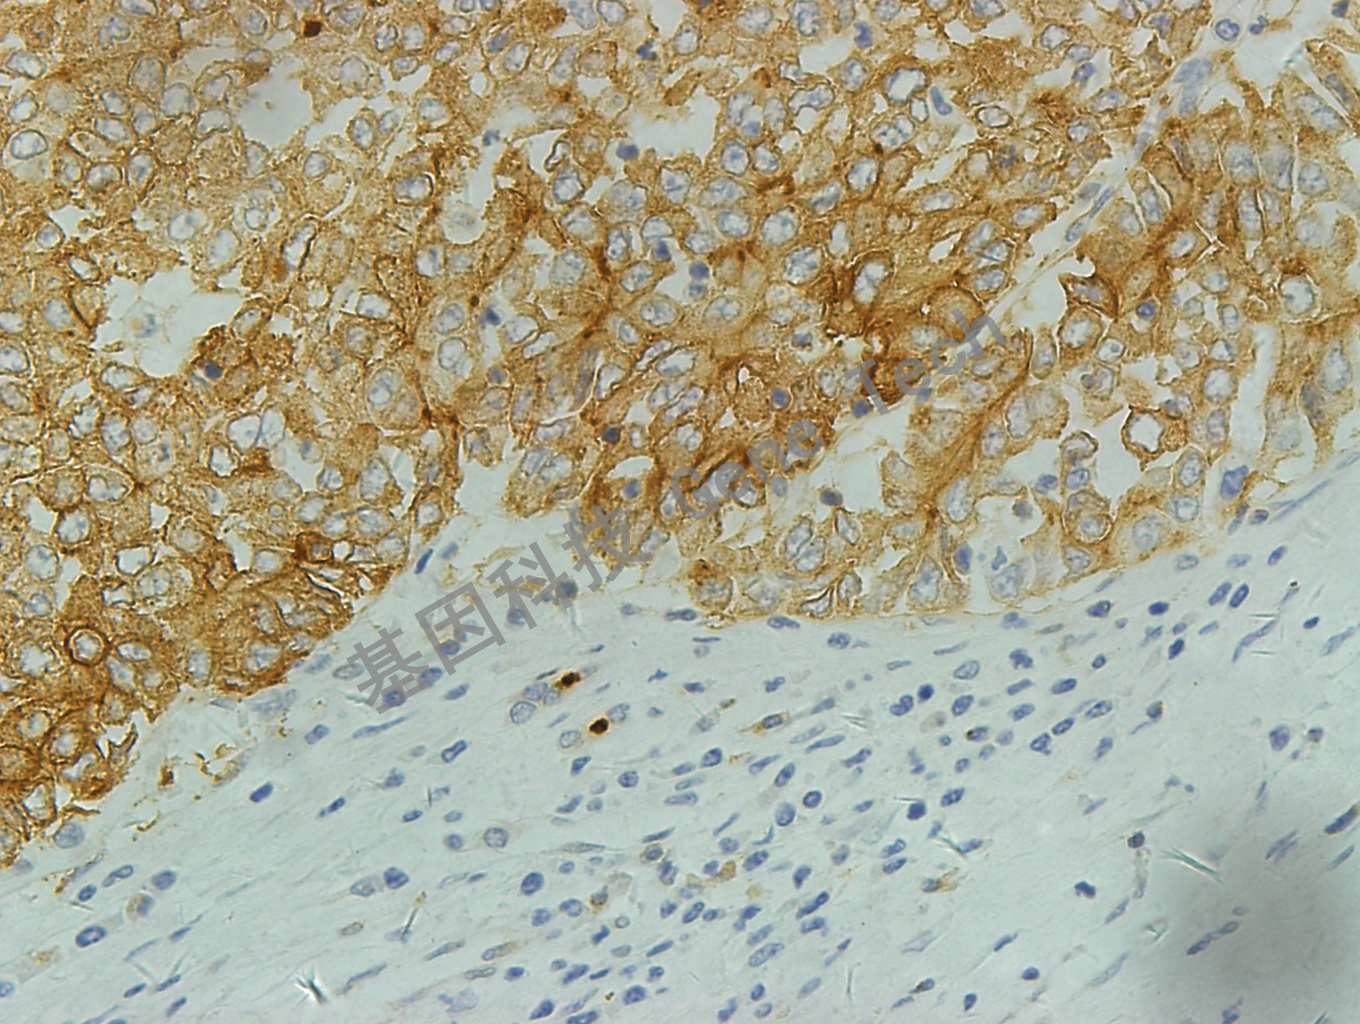

肝癌石蜡切片,用 P-glycoprotein(GT2223)染色,细胞膜阳性,DAB 显色。(10×)

肝癌石蜡切片,用 P-glycoprotein(GT2223)染色,细胞膜阳性,DAB 显色。(40×)